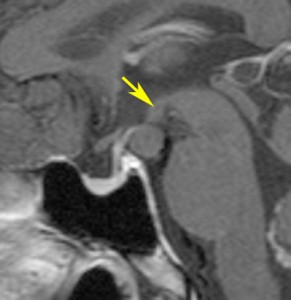

幼児期にgelastic seizureで発症

2歳でgelastic seizureを発症,6歳で思春期早発となりました

左視床下部に限局して柄を有するものです,左視索と乳頭体との境界はありません

おそらく左視床下部の機能低下と難治性の発作が原因で,左大脳半球の萎縮(あるいは発達不良)が認められます

予後がかなり不良だと判断して,2004年に摘出術をしました